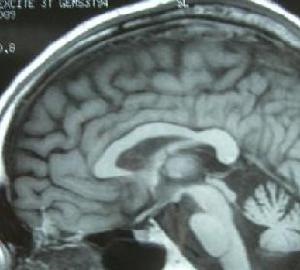

橄欖體腦橋小腦萎縮(2)小腦體積對稱變小小腦溝裂增寬加深半球小葉變細變直呈枯樹枝狀此徵象在MR軸位或矢狀位顯示較好。

(3)腦池及腦室擴大,其中以橋前池增寬最明顯,小腦及腦幹萎縮明顯者常有第四腦室擴大。

(4)其他表現:少數可有大腦皮質萎縮。